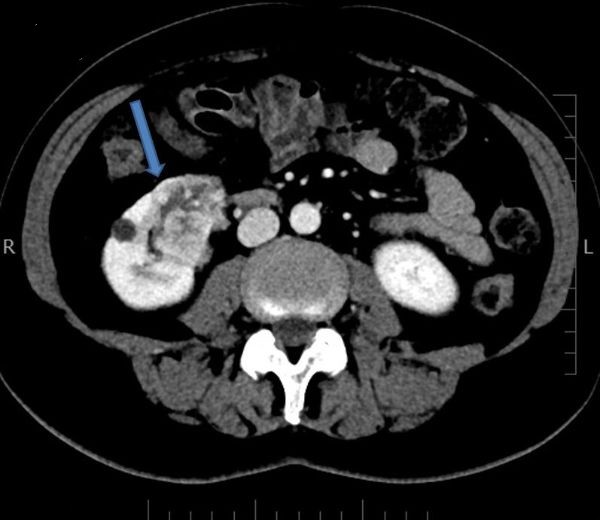

Muž 45 let – potíže s mikcí

Jste lékař urolog a přichází k vám pacient odeslán od praktického lékaře (PL). PL k Vám odesílá muže ve věku 45 let, pro nespecifické mikční potíže, které se objevily po prochlazení. Krev v moči pacient nepozoroval, lékařem to však nebylo došetřeno. Pacient nebyl doposud urologicky sledován, neléčil se.